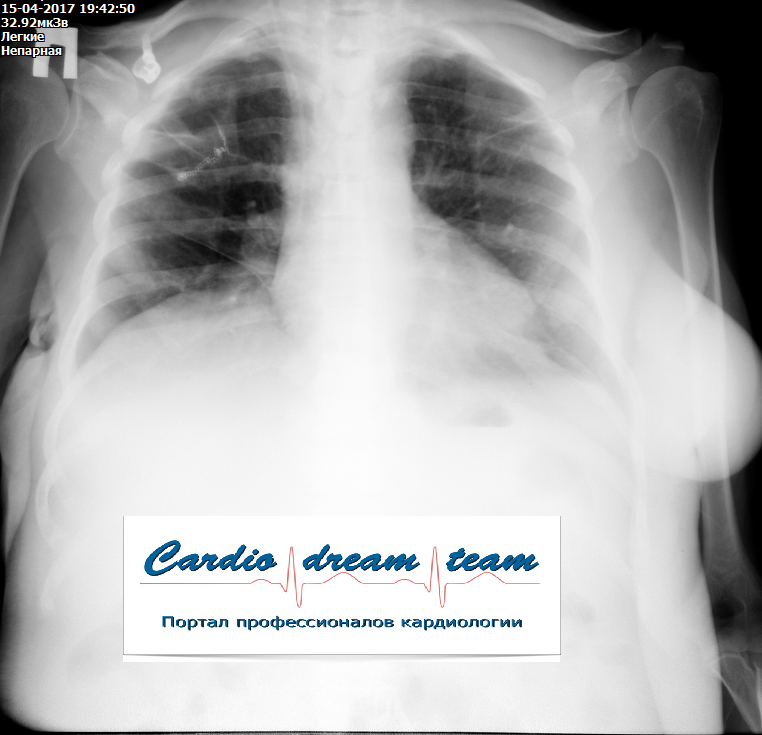

Порт для ПХТ справа

На обзорной цифровой рентгенограмме органов грудной клетки в прямой проекции легочные поля прозрачные, без очаговых и инфильтративных изменений. В верхнем легочном поле правого легкого - скрепочный шов - состояние после оперативного лечения. Легочный рисунок усилен, умеренно обогащен в прикорневых, срединных зонах, деформирован по смешанному типу. Корни малоструктурные, не расширены. Синусы свободные. Тень средостения без особенностей. Границы сердца расширены позиционно. Аорта не изменена. Тень подключичного катетера. Справа отсутствует тень молочной железы - состояние после мастэктомии справа.

Заключение: Инфильтративных изменений не выявлено. Пневмосклероз. Состояние после оперативного лечения правого легкого, мастэктомии справа.